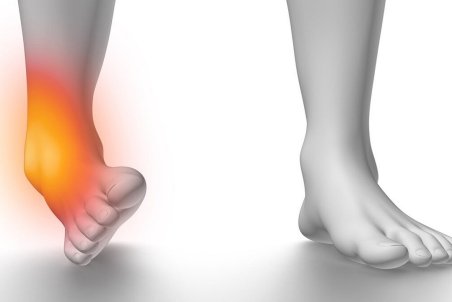

درمان پیچ خوردگی مچ پا با ورزش

دبیر انجمن فیزیوتراپی البرز گفت: فردی که دچار پیچ خوردگی مچ پا شده است در مرحله اول باید آرامش و خونسردی خود را حفظ کند.